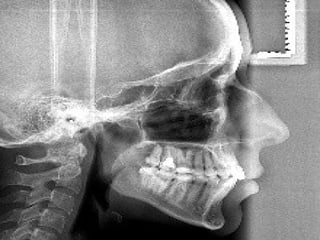

Прикус – положение зубных дуг

Физиологические прикусы:

1. Ортогнатия – резцы верхней челюсти перекрывают

нижние.

2. Прогения – наоборот

3. Бипрогнатия – наклон вперед и верхних и нижних

(резцы верхней челюсти перекрывают нижние.

4. Прямой прикус – режущие края врхних и нижних

резцов соприкасаются.

Патологические прикусы:

1. Значительная степень прогнатии – резцы верхней

челюсти перекрывают нижние.

2. Значительная степень прогении – наоборот

3. Открытый – щель между верхними и нижними

резцами.

4. Закрытый – верхние резцы полностью закрывают

5. Перекрестный – щечные жевательные бугорки нижних

коренных зубов кнаружи от верхних (а не кнутри).

 В норме верхние фронтальные (передние)

зубы выступают вперед и перекрывают нижние

на 1/3 высоты коронки, при этом наблюдается

их режуще-бугорковое смыкание. То есть,

нижние фронтальные зубы контактируют с

внутренней поверхностью верхних

фронтальных зубов своими режущими краями.

В области жевательных (боковых) зубов

присутствует полноценный фиссурно-

бугорковый контакт.

Виды профиля лица:

а — ортогнатический прикус,

б — при верхней прогнатии,

в — при нижней прогнатии (прогения).